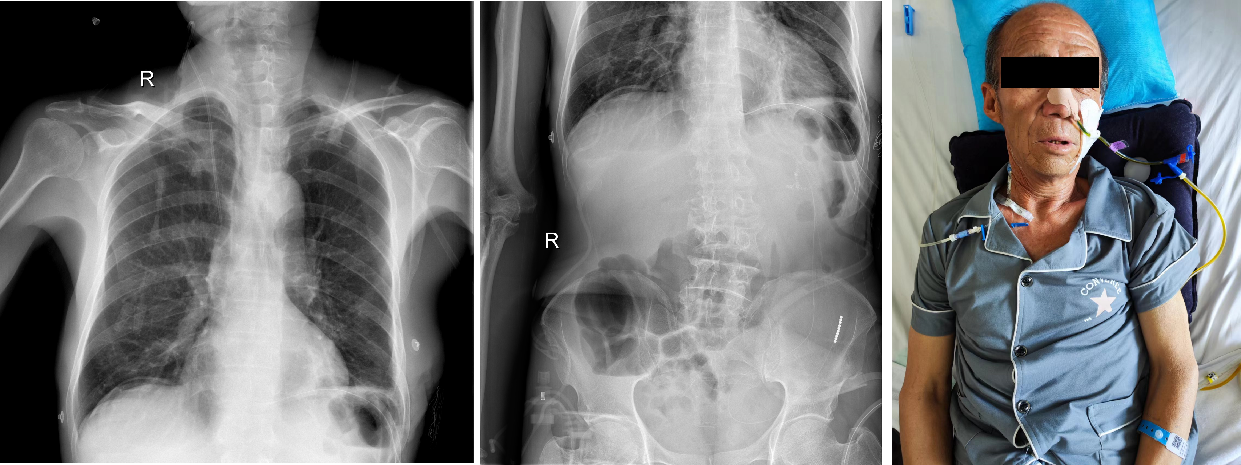

术后胸腹部X片未见明显异常,患者已开始肠内营养